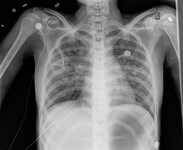

Chest x-ray of a patient with histoplasmosis, demonstrating bilateral diffuse reticulonodular infiltrates

From the personal collection of Dr David L. Goldman